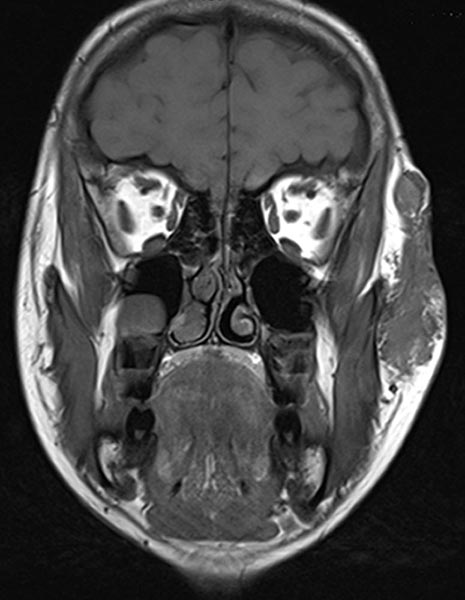

Coronal, T1-weighted MRI of the face. The venous malformation appears isointense to the musculature and is embedded in the surrounding fatty tissue.